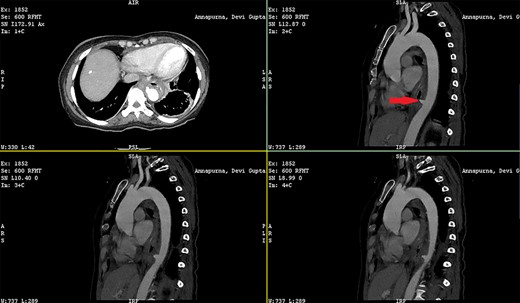

Patient 1: a 52-year-old woman, non-diabetic, non-hypertensive, was referred to the emergency with a history of large-volume, frank hematemesis (four episodes in 3 days). Positive history included recurrent cough for the past 1 year and low-grade fever for 3 months. No history of dysphagia, jaundice, abdominal distension, pain abdomen or altered sensorium. No history of chronic medications (oral anticoagulants or anti-platelets), analgesic intake or any substance abuse. She had received four units of packed red cells at an outside facility prior to admission. She was conscious, oriented, hemodynamically labile (heart rate: 110/min; BP: 86/60 mm Hg) with mild fever (99°F). General survey revealed obvious pallor. All other system examinations were within acceptable limits. Her hemoglobin (Hb) was 7.3 gram%, total leukocyte count (TLC) was 6400 cells/mm3, total bilirubin was 1.31 mg/dl and total protein was 4.75 gram%. An urgent UGI endoscopy revealed an opening in the posterior wall of the lower third of the esophagus, with a diverticulum. Inflammatory changes were noted in the diverticulum (Fig. 1). Contrast-enhanced computed tomogram (CECT) revealed erosion of the pouch into the thoracic aorta (Fig. 2), and a diagnosis of AEF with acute UGI hemorrhage was made.

Patient 2: a 48-year-old hypertensive, non-diabetic gentleman, presented to the emergency with one episode of massive hematemesis. There was no history of dysphagia, jaundice, abdominal distension, pain abdomen or altered sensorium. Past history was significant for percutaneous coronary intervention with two drug-eluting stents performed 3 years ago, for which he was on aspirin. He had normal mentation, his BP was 90/60 mm Hg and his heart rate was 120/min. A general survey revealed pallor and rest of the systemic examination was normal. His Hb was 6.1 gram% and TLC was 6300 cells/mm3. Liver function tests, coagulation parameters, renal function and electrolytes were normal. Chest X-ray was unremarkable. He was initially resuscitated with intravenous fluid, packed red blood cells and a proton-pump inhibitor infusion. An urgent UGI endoscopy revealed a large depressed ulcer with a red spot located in the middle third of the esophagus. A diverticulum was seen in the lower end of the ulcer (Fig. 7). An endoscopic clip was applied to the margin for ease of identification. CECT thorax revealed a 6 cm saccular thoracic aortic aneurysm distal to the left subclavian artery, eroding into the esophagus (Fig. 8).